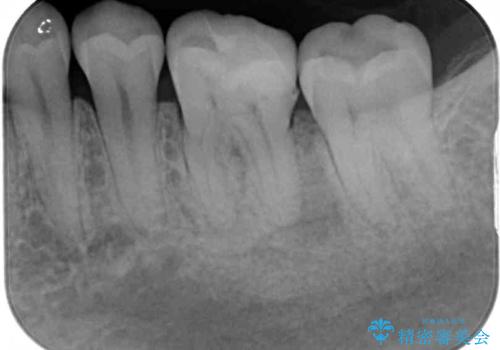

診査の結果、既に歯の神経は失活していたおり、排膿路が認められ、叩いたり触ったりしたときの痛みも確認されました。

補綴後6ヶ月経過しレントゲンを撮影したところ、遠心の歯根付近の病変が消失していることが確認できました。